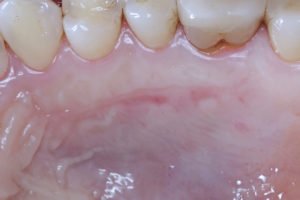

Figura 3 – A. Aspecto inicial do palato. Área doadora eleita para a remoção do ETCS. B. Após a remoção do ETCS pela técnica de bisturi de lâmina dupla descrita por Harris 1997. Na sequência,

depois de remover o enxerto para o fechamento da ferida, foi utilizado o fio de PTFE denso (Cytoplast – Osteogenics Biomedical) 4-0 com agulha de 13mm de comprimento, ½ de curvatura com o corte triangular reverso. C. Pós-operatório de sete dias. Imagem realizada antes da remoção do fio de sutura. Observar a ausência de acúmulo excessivo de biofilme bacteriano ao redor do fio de sutura. D. Pós-operatório de sete dias. Imagem realizada após a remoção do fio de sutura. Observar epitelização completa da ferida com pouca reação inflamatória tecidual proveniente do traumatismo do material de sutura e/ou do acúmulo do biofilme bacteriano. E. Pós-operatório de 14 dias após o procedimento cirúrgico. F. Pós-operatório de 30 dias após o procedimento cirúrgico. Observar o fechamento completo da ferida e ausência de reação inflamatória ou infecção no sítio doador.

Da mesma forma, as figuras 3C, D, E e F descrevem o processo de cicatrização da ferida cirúrgica palatina (área doadora). Podemos observar na figura 3C o pós-operatório de sete dias ainda com a presença do fio de sutura de PTFE denso.

Podemos observar, neste período, a ausência de grande quantidade de biofilme bacteriano ao redor do fio. Este aspecto tem um impacto clínico importante, uma vez que minimiza o risco de infecções e da formação de abcessos. Podemos notar também que o material de sutura neste período não perdeu a sua função primária de estabilização dos bordos da ferida indicando que não houve a perda da função do material. A figura 3D demonstra o pós-operatório de sete dias após a remoção do material de sutura. A figura 3E e F demonstram o pós-operatório de 14 e 30 dias

respectivamente. Observar a epitelização completa da ferida com ausência de processo infeccioso e abcessos.